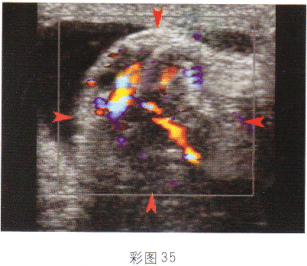

3.根據超聲圖像所示(彩圖35),最可能的診斷是

A.附睪炎

B.睪丸扭轉

C.卵巢囊腫蒂扭轉

D.子宮腺肌病

E.附睪精液囊腫

正確答案:A解題思路:附睪腫大,可見低回聲光團,形態不規則。